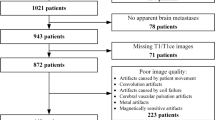

In this study, we propose an automated system for the segmentation of cancer brain metastases (CBM) using MRI images. The goal is the correlation with regards to the primary cancer site. The segmentation of CBM is a challenging task due to their wide range in terms of number, shape, size and location in the brain. We experimented with the training of a modified U-Net convolutional neural network (CNN) using N = 3474 brain image slices for training, Nv = 579 for validation and NT = 579 for testing from the public dataset BrainMetShare. The proposed model was evaluated on the testing data (NT), on a lesion-cross section basis with areas from 2.8 to 1225.7 mm2 and yielded a mean Sensitivity (SE) 0.70 ± 0.30, Specificity (SP) 0.77 ± 0.26 and Dice similarity coefficient (DSC) of 0.73 ± 0.29 across the entire dataset. The present results show the good agreement of the proposed method with the ground truth.